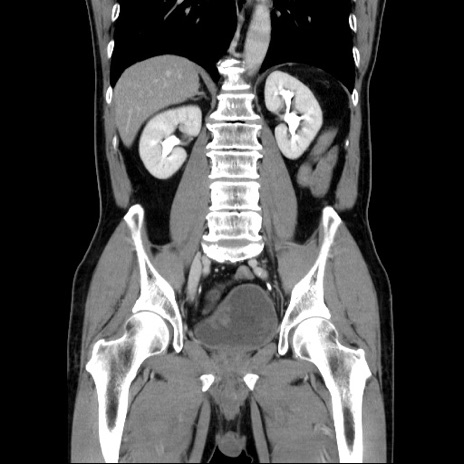

症例34(冠状断像)

【症例】60歳代 男性

【主訴】右鼠径部膨隆

【現病歴】1年程前より右鼠径部膨隆あり。自己にて還納可能だったため放置していた。3時間前より右鼠径部の脱出を認め、還納困難となり受診。

【既往歴】高血圧

【身体所見】右鼠径部に小児頭大の膨隆あり。弾性硬であり、用手還納は困難。左鼠径部にも膨隆を認める。脱出はなし。